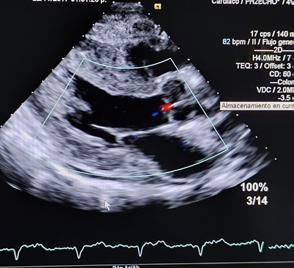

Un ultrasonido del corazón, también conocido como Ecocardiograma, es una técnica de examen médico que utiliza ondas de ultrasonido para crear imágenes del corazón en movimiento y de los vasos sanguíneos (en tiempo real), aplicando gel en el área cardíaca y luego se mueve el transductor sobre la zona.

Una computadora convierte las ondas sonoras en imágenes del corazón; es una herramienta inofensiva, no invasiva, relativamente barata, ampliamente disponible y una de las más utilizada en la cardiología porque permite detectar y evaluar una gran variedad de enfermedades tanto en la estructura como de la función cardíaca, permite verificar si el tejido cardíaco recibe suficiente flujo de sangre y oxígeno, detecta anomalías como aumento del grosor de las paredes, aumento del tamaño del corazón y si éste tiene la suficiente fuerza para bombear la sangre a todo el cuerpo; evalúa en tiempo real la función y anatomía del corazón, el ta-

maño de las cavidades, defectos en las válvulas, en la aorta y/o arteria pulmonar; además permite medir el flujo sanguíneo dentro del corazón y los grandes vasos, detecta problemas estructurales o funcionales así como monitorea el estado del corazón después de un evento cardiovascular, cirugía o tratamiento; así como detectar cardiopatías congénitas. También puede detectar otros problemas como derrame pericárdico, pericarditis, disección de la aorta, etc. El estudio lo realiza un Cardiologo o Cardióloga, especialista en imágenes cardíacas; realiza e interpreta el estudio y en base en los resultados puede diagnosticar enfermedades cardíacas, recomen-

dar o modificar tratamientos como medicamentos o cirugías; su médico puede solicitar un Ecocardiograma si como paciente presentas: